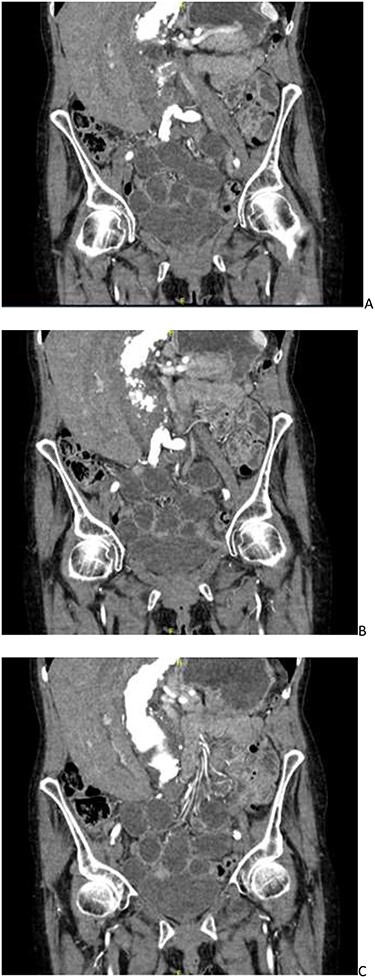

CT angiogram showing a left-sided obturator hernia; (A–C) progressing posteriorly in a coronal plane.

She was suspected of having a worsening AAA, and thus a computed tomography (CT) angiogram was organized. Overnight this was reported as a stable AAA without rupture with incomplete small bowel obstruction, possibly due to faecal loading of the caecum. The patient was then treated as such with laxatives and an enema. The patient did not improve, and clinically, her symptoms did not correlate with the CT findings. The CT report was re-discussed the following day and an addendum was made. The CT scan was now reported as a mechanical small bowel obstruction secondary to a left obturator hernia, which contained a small segment of ileum as seen in Fig. 1.